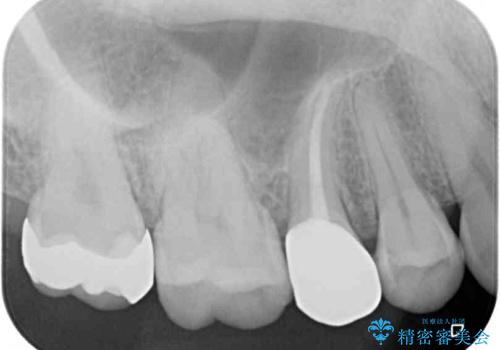

- 近々海外へ転居するとのことで、事前に処置をしておくべきむし歯がないか、気にして来院された患者様です。

レントゲン写真などから、速やかに処置を行うべき歯が2歯あったため、それぞれセラミックインレーとPGAインレー(ゴールドインレー)にて修復治療を行うこととしました。